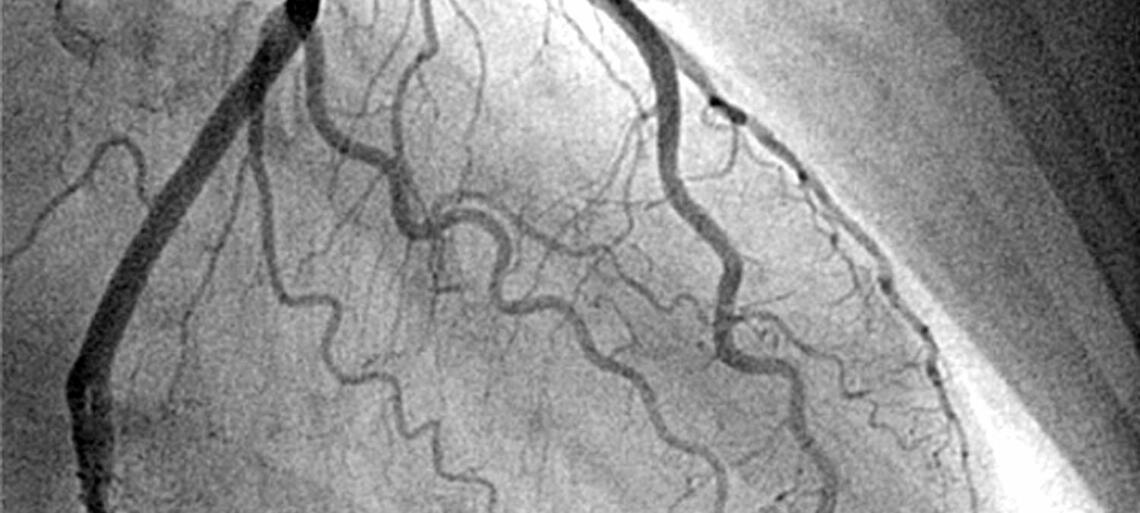

La coronarografia è un esame radiologico che, mediante l’utilizzo di un mezzo di contrasto, consente la visualizzazione delle arterie coronarie ossia delle arterie che portano il sangue al cuore. Si svolge in sala di emodinamica.

Essa rappresenta il gold standard nello studio dell’anatomia coronarica e, se necessario, può essere accompagnata da studi ecografici intravascolari (IVUS) e studi funzionali (FFR, iFR, QFR…) se indicati.

Sotto controllo radioscopico i cateteri diagnostici vengono fatti avanzare fino all’origine delle coronarie. Con l’iniezione di una piccola quantità di mezzo di contrasto si ottiene la visualizzazione dei rami delle coronarie e ciò consente di valutare la presenza o meno di punti di restringimento.